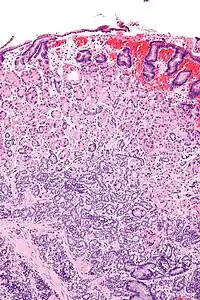

![]() Micrografía de un tumor neuroendocrino gástrico. Tinción H&E. | ||